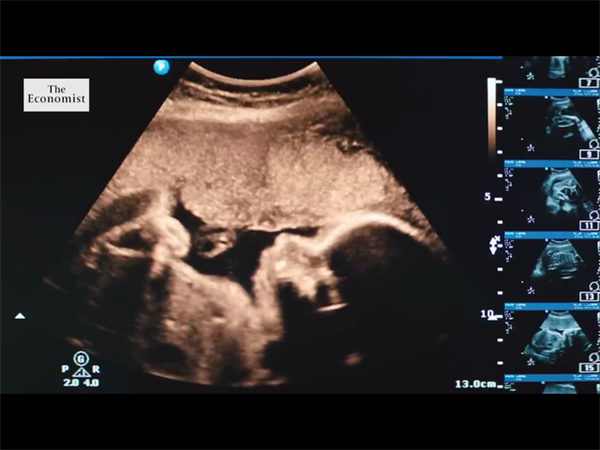

如今,随着国家经济的发展,出行也变得十分便捷,有不少不孕不育夫妇都会选择到国外做试管婴儿,其中,不少夫妇会选择在格鲁吉亚做试管,但相比于东南亚国家而言,大多数人对格鲁吉亚相对陌生,那么格鲁吉亚试管婴儿有哪些优势呢?下面来具体了解一下吧。

不少人之所以放弃在国内做试管,而选择去格鲁吉亚进行试管助孕,归根结底还是看重了格鲁吉亚试管婴儿技术的优势,不过很多不孕不育夫妻并不是特别了解,下面就为大家着重解释一下格鲁吉亚试管婴儿6个绝对优势完胜国内。

格鲁吉亚试管专家介绍:国内医院基本上是运用第一代和第二代试管,医院人满为患,排队的周期还在不断加长。所谓第三代试管婴儿也称胚胎植入前遗传学筛查确诊(PGS/PGD),指在胚胎移植前,取胚胎的遗传物质进行剖析,确诊是否有异常,筛选健康胚胎移植,防止遗传病传递的办法。

而据现在统计,全世界遗传性疾病有4000余种,现在格鲁吉亚的第三代试管婴儿运用PGD技能最大程度筛查出125种遗传性疾病,没有任何的约束条件任何人都可以做,并且可以合法选择生男生女。